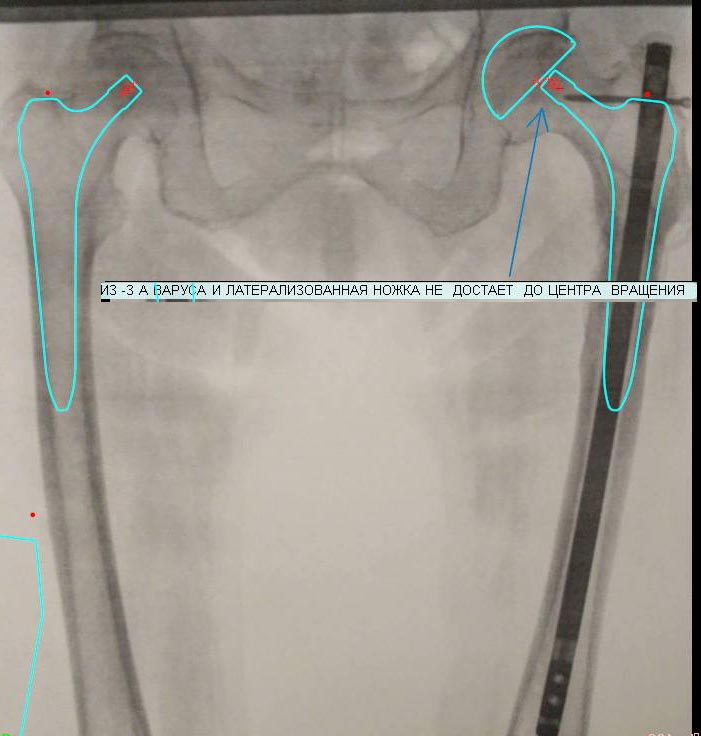

Конечно, это можно отнести к сложному первичному эндопротезированию, но проблем не должно быть. Если вы хотите дотянуть до центра вращения, то примерьте ножек Споторно, хотя я думаю что и с Цваймюллера проблем не будет

Какую бы Вы ножку не брали, ситуация такая же. А со Споторно, ее прямой спинкой - прощай большой вертел :) Это легко говорится, да не просто делается :)

Надо понимать, что сохранить вертел практически невозможно. Если это принципиально, то сделайте во время эндопротезирование вальгизирующую остеотомию и используйте ножек Вагнера или Цваймюллера

корректно поставить эндопротез в этой ситуации - задача очень сложная, без остеотомии не обойтись, будет много проблем и этом варианте (плохое качество кости выше остеотомии и непонятный склероз ниже и тд).Нужны ли такие приключения при весьма неочевидных показаниях для протеза у пожилого человека?Гораздо более прогнозируемый вариант и менее травматичный - остеотомия и исправление деформации, не столь важно чем, гвоздем, клинком или DHS. Если и зайдет речь об артроплатике после этого, то будет много проще, фактически будет обычное первичное эндопротезирование без приключений и неожиданностей.